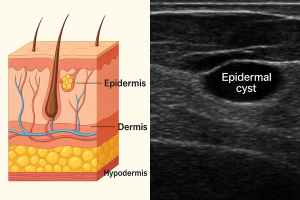

🔹 Caso 1: un pequeño bulto en la piel

Una paciente joven acude preocupada por un pequeño bulto que notó hace un par de días en la parte baja del abdomen. Al explorarlo no dolía, pero se palpaba firme, bien delimitado. ¿Podría ser un ganglio? ¿Un quiste?

La ecografía mostró un quiste epidérmico superficial, bien delimitado, sin signos inflamatorios. Bastó una imagen rápida para tranquilizar a la paciente y evitar pruebas innecesarias.

Recordar por pequeño que es el bulto, debemos palpar bien, para colocar la sonde lineal correctamente, y ajustar los parametros de profundidiad muy superfecial, con la frecuencia al maximo, con centrar el foco y la gancncia. Una vez en el foco adecuado hacer los zum necesarios.